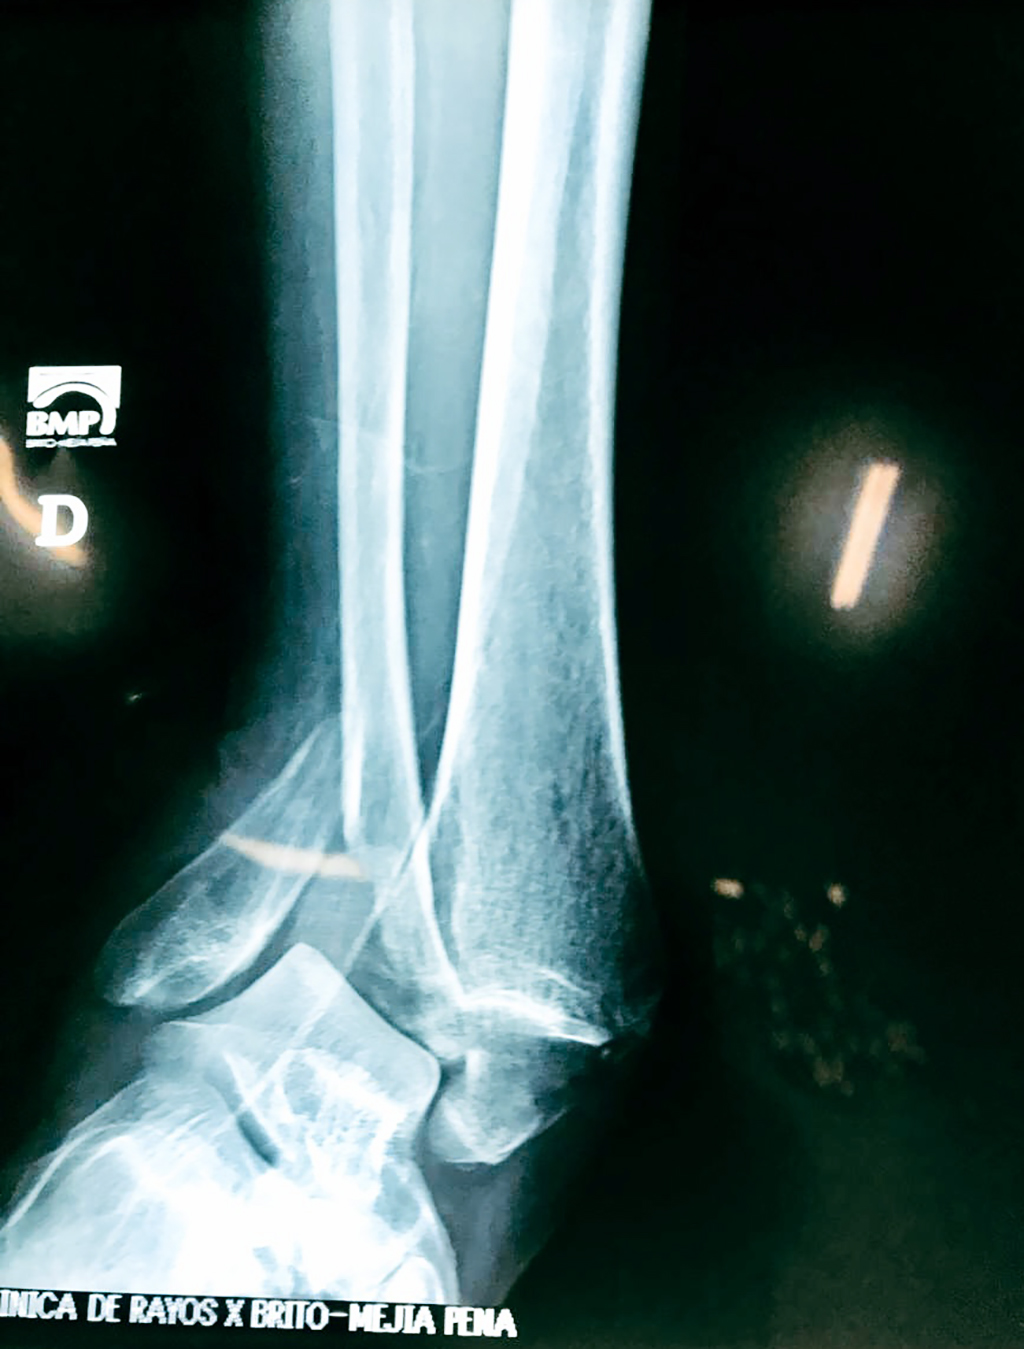

Una fractura de tobillo es la rotura de uno o más de los huesos del tobillo. Estas fracturas pueden ser:

- Parciales (el hueso está sólo parcialmente fisurado, no del todo).

- Completas (el hueso está perforado y está en 2 partes).

Cuando se necesita cirugía, es probable que esta implique el uso de clavijas de metal, tornillos o placas para sostener los huesos en su lugar mientras la fractura se consolida. Los elementos de soporte pueden ser temporales o permanentes.